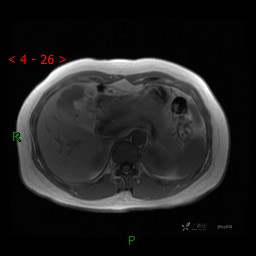

上腹部MRI平扫(同反相位)